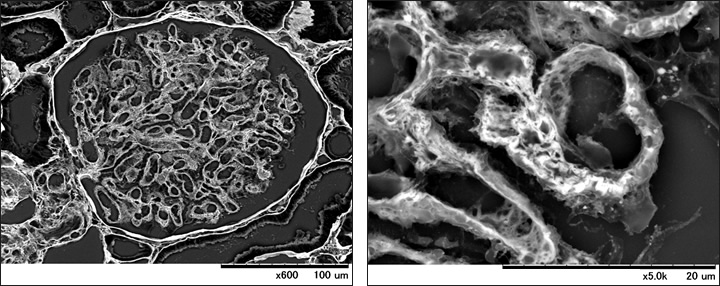

Observation data of the renal glomerulus sections.

The specimen was PAM-stained for light microscope observation, not prepared for any electron microscope observation.

It was directly observed with the specimen on a slide glass. Thanks to PAM-stained contrast, basal membrane observation enables us to check shape change of the lesion.